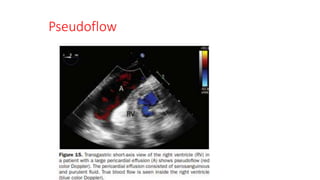

Pseudoflow

• Motion of fluids other than blood, such as ascites, amniotic fluid,

pleural effusion, and urine can be imaged with CFD

• This “pseudoflow” is an artifact because spectral imaging

will not typically show characteristic arterial or venous waveforms.

• Pericardial effusions seen during an echocardiographic examination

may demonstrate flow because of their proximity to the heart.

Pseudoflow • Motion offluids other than blood, such as ascites, amniotic fluid, pleural effusion, and urine can be imaged with CFD • This “pseudoflow” is an artifact because spectral imaging will not typically show characteristic arterial or venous waveforms. • Pericardial effusions seen during an echocardiographic examination may demonstrate flow because of their proximity to the heart.

• 41.